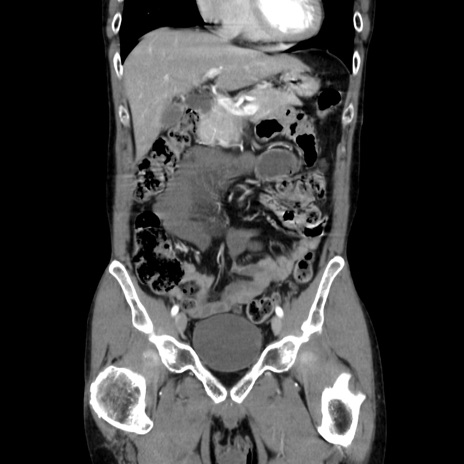

症例37(冠状断像)

【症例】40歳代 男性

【主訴】腹痛

【現病歴】4時間ほど前に電車に乗車中に臍部上より腹痛出現。徐々に増悪し起立困難となり、救急外来受診。生ものは数日食べていない。今朝お雑煮を食べた。

【身体所見】BT 36.8℃、BP 117/84mmHg、HR 91/min、SpO2 97%、苦悶様、腹部:臍上部広範囲圧痛あり、反跳痛±

【データ】WBC 8100、CRP 0.03